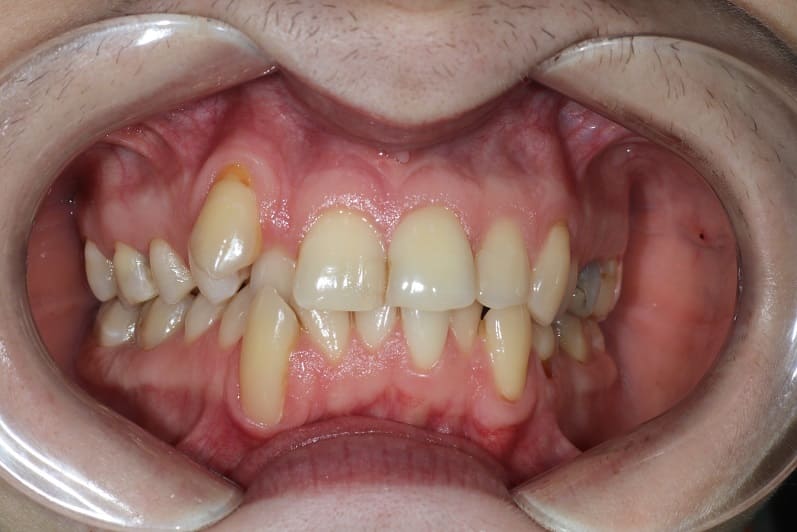

Ортодонтическое лечение на самолигирующейся брекет-системе

Ортодонтическое лечение на самолигирующейся брекет-системе заняло 2,5 года.